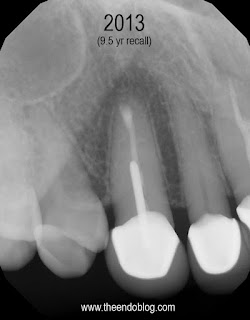

Apicoectomy completed, no root fractures seen with microscope. MTA retrofill.

9.5 year recall.  Tooth is fully functional, asymptomatic with radiographic healing.  Apicoectomy has preserved the tooth and the periodontium for an extended period of time.